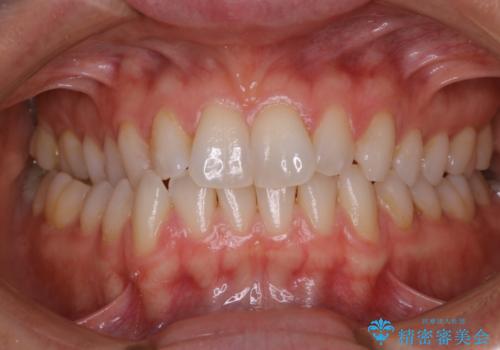

PMTCで笑った時の口元を自然に明るくしたい